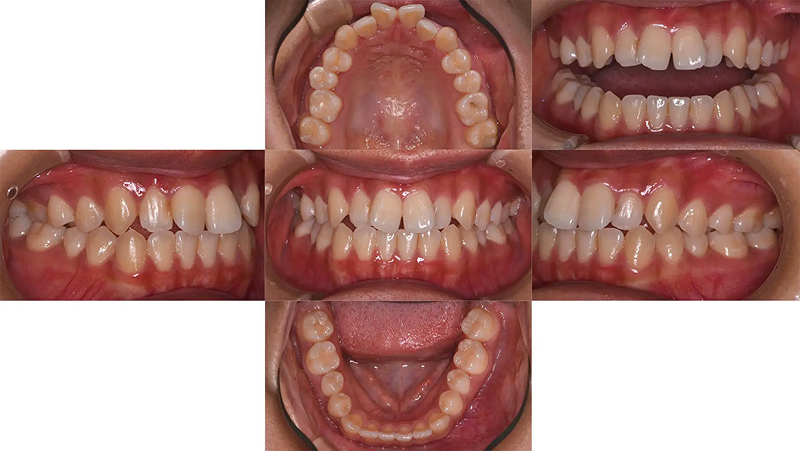

Case02マウスピース型矯正で前歯の凸凹を改善した部分矯正

前歯の凸凹が気になると受診されました。ただ、従来の矯正装置は付けたくないとのことで審美矯正を希望されました。本来なら全顎矯正の適応ですが、費用の兼ね合いもあり、前歯の凸凹だけ治療しても、審美的な改善はもちろん、機能的にも問題ないと診断しました。14枚(上下で28枚)以内のインビザライン ライトを適応しました。短期間できれいになったと大変満足していただけました。

口元比較

Before

After